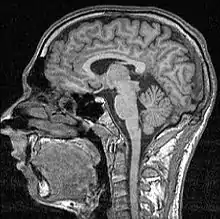

Neurobiological evidence

Evidence from neural imaging supports the warm-glow effect. Recent research using functional magnetic resonance imaging of subjects making donation decisions identifies the subgeneal area and the ventral striatum as regions associated with social giving.[59] The mesolimbic rewards of giving are neurobiologically similar to receiving material rewards.[4][59] While there is some evidence for a "literal warm glow" — in which an individual's perceived thermal state is elevated by the act of giving due to activation in the insula[60] — the more general consensus across the psychological and neurobiological fields is that helping others makes people happy through the release of the oxytocin[59] and endorphins.[16]